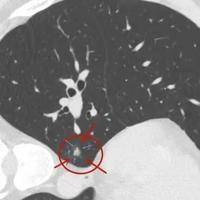

女性有一个18mm大小的良性肺结节适合做试管吗?

问题描述:昨天去做了生育检查,从结果来看我自然生育会比较困难,因此就建议我们做试管治疗。回家后我了解到辅助生育对身体素质也会有一定要求,但我昨天查出来有一个18mm大小的肺结节,好在是良性的。想问问大家这个情况适合做试管吗?最佳回答:有18mm的良性肺结节的情况下能够做试管治疗需要综合多种因素来决定。一般会从结节的性质、大小、位置以及患者的整体健康状况。一般来说,肺结节本身并不影响受精卵在体外受精...